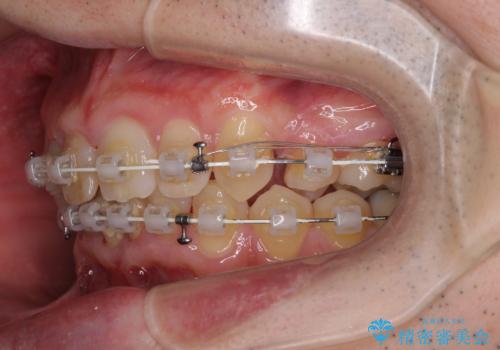

上顎歯列の叢生が著しかったため、上顎左右第一小臼歯2本を抜歯し、目立たないワイヤー装置にて治療を進めることとしました。

矯正治療後にはオーダーメイドタイプのオールセラミッククラウンを装着し、自然な口元に仕上がりました。